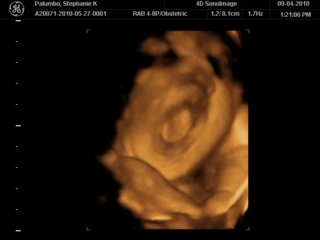

This was me back in early September